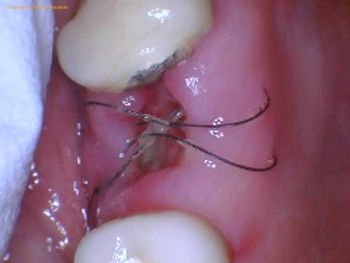

Stitch gums After tooth extraction

Wisdom teeth stitches, also known as sutures, are used by oral surgeons to close the incision made during wisdom teeth removal surgery. These stitches play a crucial role in helping the wound heal properly by holding the tissues together. There are different types of stitches used in dental procedures, including dissolvable and non-dissolvable sutures. Dissolvable stitches, as the name suggests, are designed to break down and be absorbed by the body over time, eliminating the need for removal by the dentist.

There are two main types of wisdom teeth stitches: absorbable and non-absorbable. Absorbable stitches are made from materials that the body can naturally break down and absorb. These stitches are typically used for procedures where the incision is inside the mouth and cannot be easily accessed for removal. Non-absorbable stitches, on the other hand, are made from materials like silk or nylon and need to be removed by the oral surgeon after the healing process is complete.